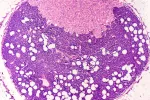

En los ensayos aplicaron el ZD2 a la superficie de la molécula de fulereno, y esto permitió que el péptido identificase específicamente la proteína del cáncer EDB-FN, que está relacionada con la invasión de un tumor, la metástasis y la resistencia frente a los fármacos, y se manifiesta de forma notoria en la matriz que rodea las células malignas en muchas formas agresivas de cáncer.

En las pruebas realizadas a seis modelos de ratones la resonancia magnética detectó el cáncer de mama en todos los casos, y se observó que la señal originada por la acumulación de moléculas de contraste en tres tipos de cáncer de pecho agresivos era notablemente más brillante, mientras que cuando se trataba de tumores de crecimiento lento, esta señal era débil. Los autores del estudio continúan investigando con el objetivo de encontrar la forma de disminuir los costes de producción del nuevo agente para facilitar su incorporación a la práctica clínica.